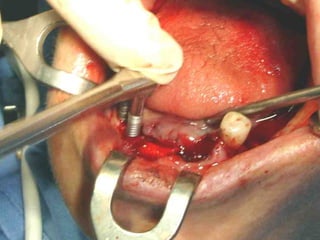

Neumólogo: Dr. CrescencianoGonzález OlivaresNeumólogo: Dr. Crescenciano González Olivares

• 398.

Trismus importante debidoa queTrismus importante debido a que El tumor ya rompió el hueso com-El tumor ya rompió el hueso com- Pacto de la cara interna de laPacto de la cara interna de la Mandíbula y empezó a tomar elMandíbula y empezó a tomar el Músculo pterigoideo interno.Músculo pterigoideo interno.

• 412.

Area de lisisósea a nivel de la líneaArea de lisis ósea a nivel de la línea Miliodes que contracturó los músculosMiliodes que contracturó los músculos Milohioideo y pterigoideo internoMilohioideo y pterigoideo interno Dificultando la deglución y determinandoDificultando la deglución y determinando Trismus importante.Trismus importante. Pieza en proceso de examen por histopatologíaPieza en proceso de examen por histopatología